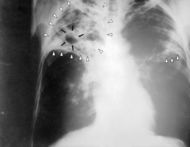

| Chest X-ray of a patient suffering from Tuberculosis | |